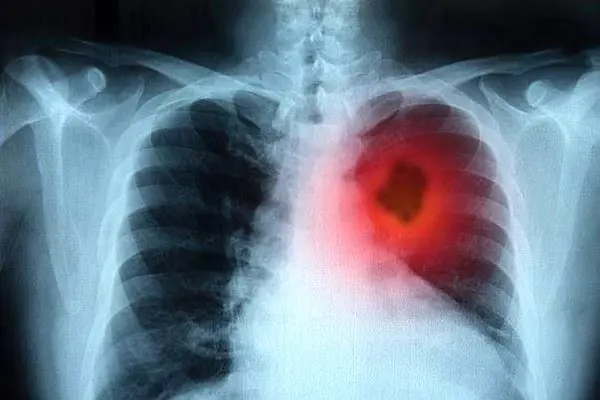

رکنا: به تازگی روشی نوین برای بیوپسی و از بین بردن تومورهای سرطان ریه ابداع شده است. در این روش با کمک یک سوزن و انرژی فرکانس رادیویی تومور سرطانی از بین می رود.

به گزارش دیلی میل، روشی نوین برای درمان سرطان ریه ابداع شده که برای تشخیص و ویران کردن تومورهای دور از دسترس به کار می رود. به این ترتیب می توان هزاران نفر از مبتلایان به این بیماری خطرناک را بدون جراحی درمان کرد. در این روش پزشکان به وسیله یک سوزن داغ تومورها را خرد می کنند.

این نوع درمان فرسایش با فرکانس رادیویی( radio frequency ablation )نامیده می شود و همزمان با آن یک بیوپسی نیز انجام می شود. در این فرایند قطعات کوچک تومور سرطانی برداشته و آزمایش می شوند تا میزان شدت و گسترش بیماری در بدن آزمایش شود.